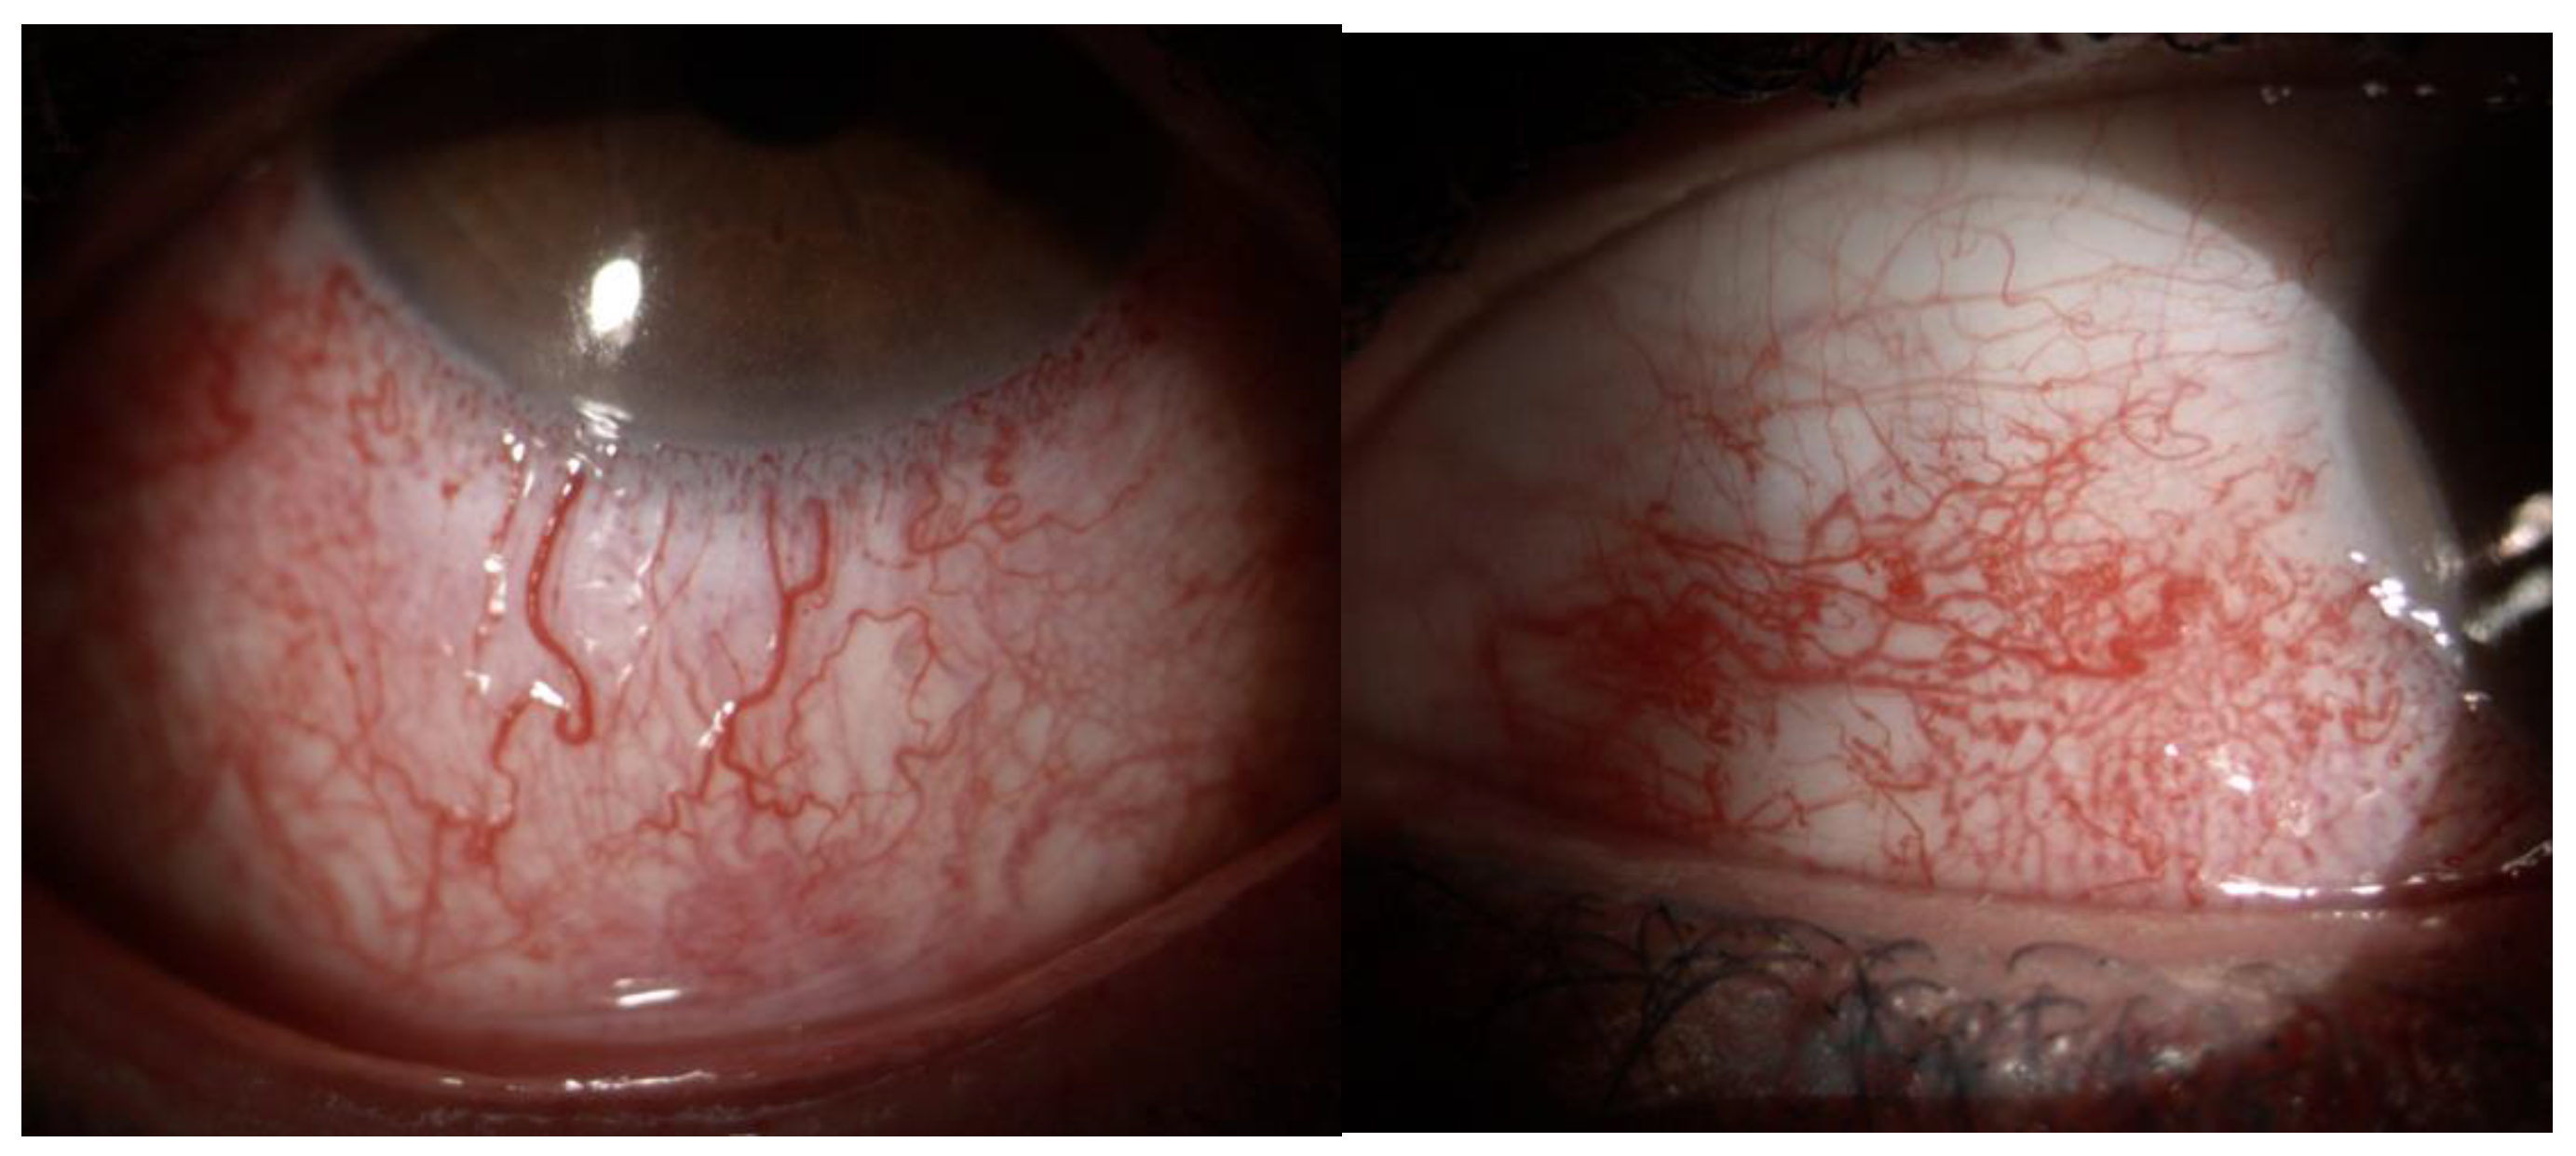

- Ciancimino, C.; Di Pippo, M.; Rullo, D.; Ruggeri, F.; Grassi, F.; Scuderi, G.; Abdolrahimzadeh, S. An Update on Multimodal Ophthalmological Imaging of Diffuse Choroidal Hemangioma in Sturge-Weber Syndrome. Vision 2023, 7, 64. [Google Scholar] [CrossRef] [PubMed] [PubMed Central]

- Zhao, Z.; Xu, L.; Ding, X.; Wu, Y.; Zhu, X.; Fu, Y.; Guo, W. Optical Coherence Tomography Angiography of Perilimbal Vasculature in Port-Wine Stain and Sturge-Weber Syndrome Patients. Investig. Ophthalmol. Vis. Sci. 2020, 61, 43. [Google Scholar] [CrossRef] [PubMed] [PubMed Central]